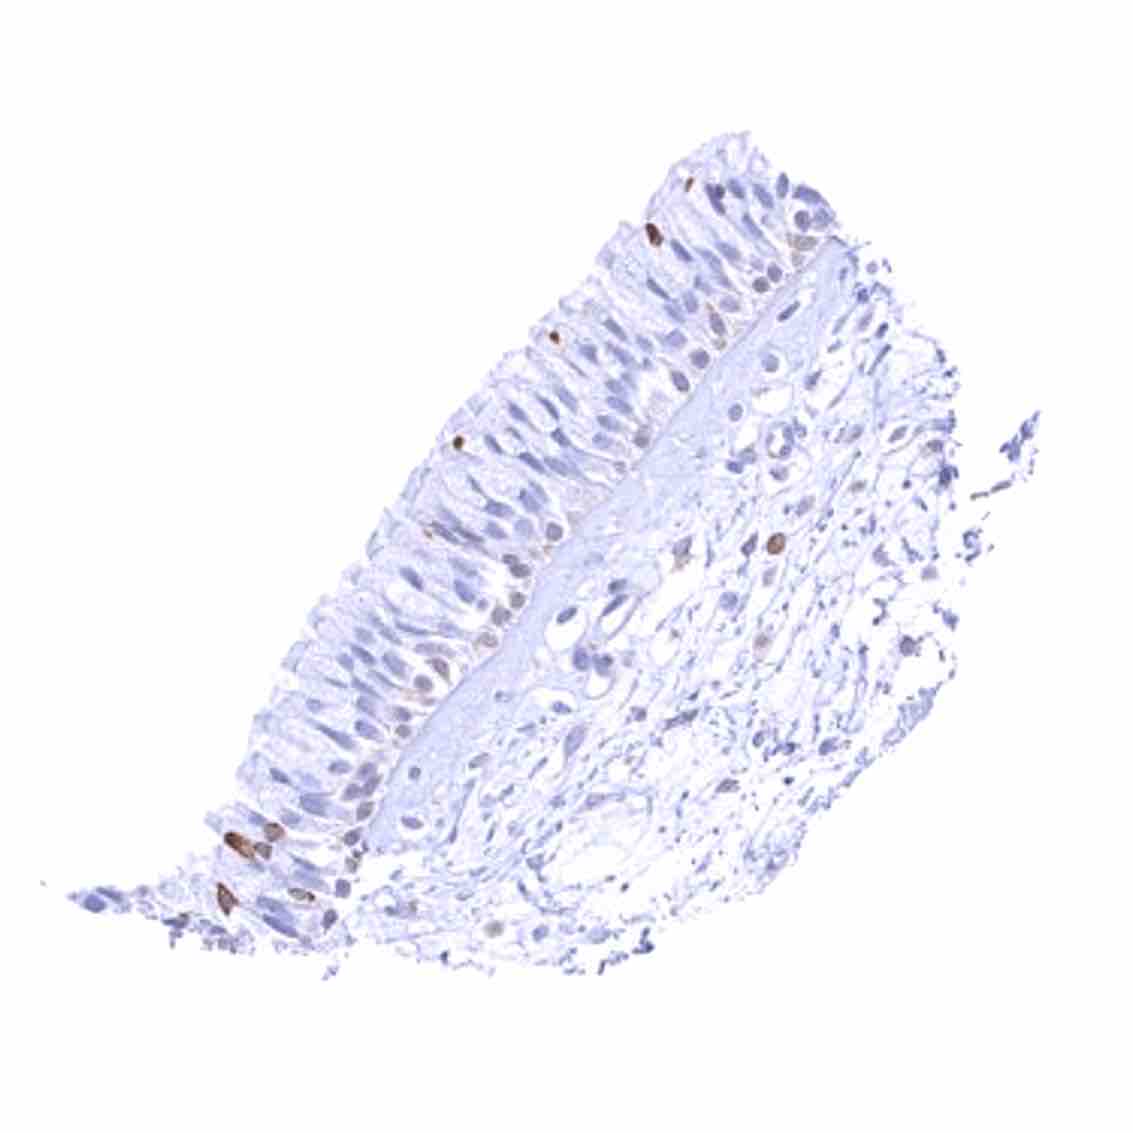

Duodenum, mucosa – Cytoplasmic bcl-2 staining is largely limited to lymphocytes. The epithelium is mostly negative, but a weak staining occurs in some crypt cells.